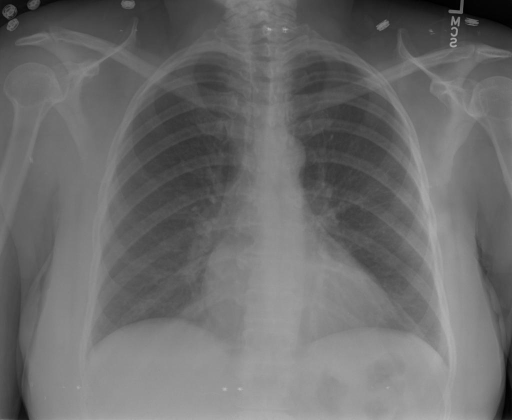

|X光影像|诊疗报告(医生)|XrayGLM|

||根据X射线图像,心脏大小正常,肺部看起来很清晰。已经排除了肺炎、积液、水肿、气胸、腺病、结节或肿块的存在。该发现表明一切正常。换句话说,总体印象是胸部正常。|X光片显示,心脏大小正常。肺部没有气胸或胸腔积液的证据。骨骼结构看起来没有任何异常。总的来说,X光片表明没有发现急性心肺疾病的迹象。|